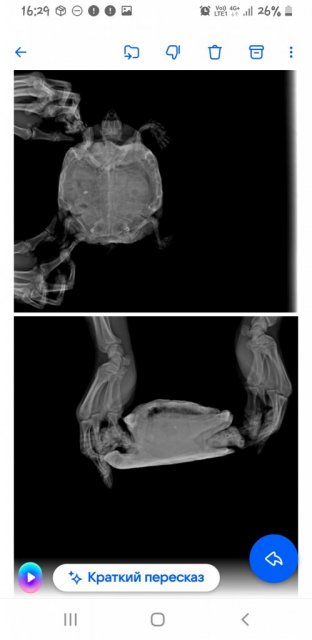

Александр Вдовин Ваше имя: Александр Локация: РФ, Самара Опубликовано: 24 августа 2024 Опубликовано: 24 августа 2024 Не знаю ее возраста, т.к. приползла ко мне на дачу 12 лет назад подростком Недели 3 назад обратил внимание на тяжелое дыхание(возвратно-поступательные движения передних лап с большой амплитудой). Примерно тогда же она стала мало есть и перестала какать. К тому же перестала использовать задние лапы Я живу в Самаре. Эти 3 недели я попадал к людям в ветклиниках, которые считают себя герпетологами. Намучали они моего питомца и отняли время, дарив пустую надежду Сегодня поехал в "Симсон", и черепахе сделали рентген в 3 проекция.Сказали, что всё ужасно. Подскажите сильно опасно ли в данной ситуации консервативное лечение? Возможно ли попасть на операцию к Дмитрию Борисовичу Васильеву без длительного ожидания, если уж без операции никак.Я оставил заявку на прием к нему на сайте " Белый клык" и не знаю увидит ли он её. Мне пока не ответили. К тому же сегодня суббота.Я теряю время. И в Москву я очень быстро добраться не смогу, т.к. мне на самолете нельзя летать.

Консультанты moth Ваше имя: Мария Локация: Москва Опубликовано: 24 августа 2024 Консультанты Опубликовано: 24 августа 2024 @Александр Вдовин здравствуйте! по рентгену тут действительно всё плохо в плане лёгких, их просто нет - они либо пережат содержимым жкт, либо какая-то другая проблема, тут уже должен непосредственно врач-герпетолог хороший смотреть. В Саратове есть хороший герпетолог-хирург, туда Вам проще доехать будет? https://cherepahi.ru/servisy/catalog/rossiya/spravochnik-saratovskaya-obl-saratov/ у них есть стационар, где можно черепаху на лечение оставить

Александр Вдовин Ваше имя: Александр Локация: РФ, Самара Опубликовано: 29 августа 2024 Автор Опубликовано: 29 августа 2024 Какие еще косвенные признаки бывают? Газов у нас на снимке не наблюдается,но легкие как будто чем-то прижаты. Хотя нам Валерия Николаевна пневмонию продиагностировала Поэтому точно узнать прижаты они или поражены точно определить сложно. Пневмония только снизу - тоже странно А чем они бывают прижаты ещё, кроме газов кишечника? Не могу найти информацию нигде Вот снимки. Очень похоже, что они с разными настройками

Консультанты moth Ваше имя: Мария Локация: Москва Опубликовано: 29 августа 2024 Консультанты Опубликовано: 29 августа 2024 @Александр Вдовин тут само качество снимков плохое и мелкое из-за разрешения телефона. Лёгкие могут быть пережаты не только газами, но и скоплением кала в жкт, увеличенным мочевым пузырём. Тут придётся кт ждать.

Консультанты moth Ваше имя: Мария Локация: Москва Опубликовано: 29 августа 2024 Консультанты Опубликовано: 29 августа 2024 @Александр Вдовин да, может, если есть закупорка солями но не думаю, что это ваш случай, тут скорее всё-таки либо жкт, либо проблема с лёгкими